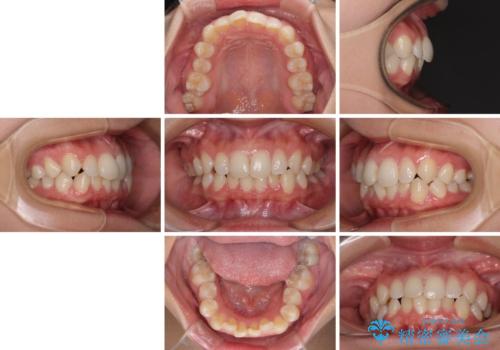

- 前歯のデコボコと歯肉に埋もれている奥歯を気にして来院された患者様です。

インビザラインでの治療を希望されていましたが、左右の下顎大臼歯が歯肉に埋もれており、特に右側は歯軸が顕著に傾斜していたため、インビザライン単独での治療は困難と判断し、ワイヤー装置を併用することとしました。

ワイヤー装置での下顎臼歯改善には時間がかかることが予想されたため、下顎のワイヤー矯正と並行して上顎をインビザラインで整え、その後インビザラインにより上下歯列を整える矯正治療を行うこととしました。

ワイヤー装置を併用したことで、レントゲン写真からも分かるとおり歯軸をしっかりと改善させることができました。